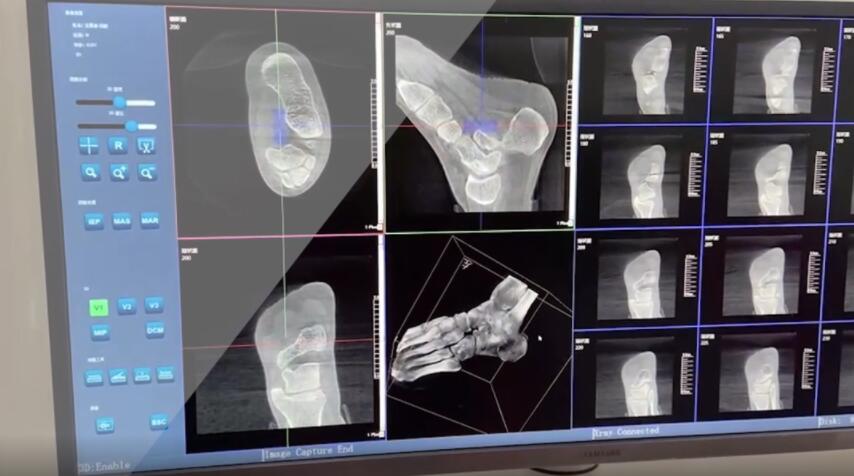

在術(shù)前,我們需要做三維掃描的CT檢查,我們必須要有CT的片子,還要有三維的重建。

在術(shù)中,我們?cè)趺慈ヅ袛嚓P(guān)節(jié)面平不平整呢?常規(guī)的正側(cè)位影像是不能判斷的。有些醫(yī)生為了準(zhǔn)確的判斷,可能會(huì)選擇做開(kāi)放性的手術(shù),把關(guān)節(jié)暴露出來(lái),在眼睛的直視下判斷關(guān)節(jié)面平不平整。但是關(guān)節(jié)全部打開(kāi),無(wú)疑增加了病人的創(chuàng)傷,而且增加了患者的恢復(fù)時(shí)間。所以如果在術(shù)中我們有三維影像的支持,對(duì)醫(yī)生做手術(shù)而言就會(huì)事半功倍,而且能夠大大的增加手術(shù)準(zhǔn)確度,增加患者術(shù)后的預(yù)后。所以在術(shù)中有三維影像的支持是非常必要的!